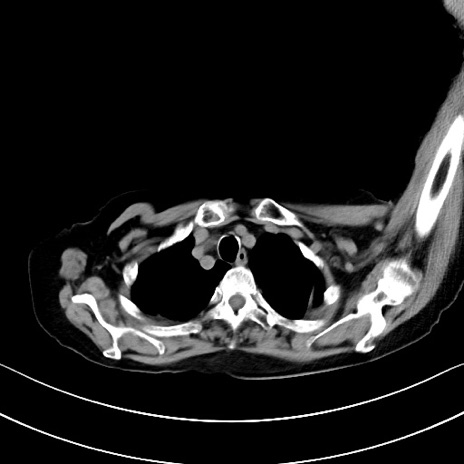

横断像